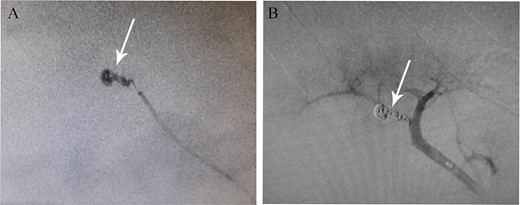

Eight days after discharge, he presented to the ED complaining of gross massive hematuria. He went into cardiac arrest, and cardiopulmonary resuscitation (CPR) was performed. His hemoglobin had dropped from 11.9 on the day of previous discharge to 6.8. He was later stabilized and started on blood transfusion and was put under close observation until he became hemodynamically stable. He underwent emergent renal arteriography, which showed RAP, and selective angioembolization was done (Fig. 2). Hematuria subsided after 2 days, and the patient was discharged. After 3 months, the patient was well and still in stage I CKD.

(A) Pseudoaneurysm seen on renal angiography. (B) The pseudoaneurysm following angioembolization.